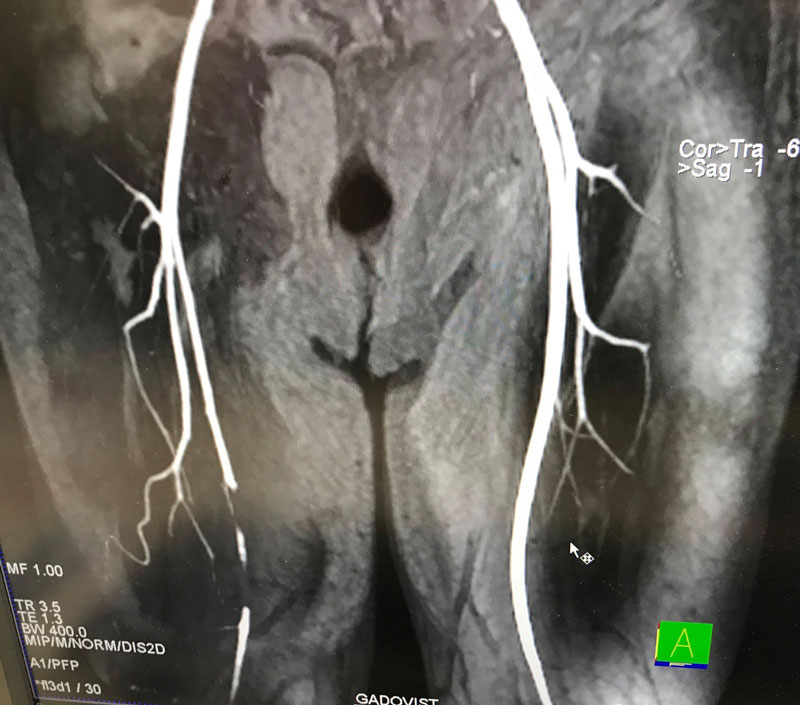

,,Spitalul Județean de Urgență Târgu-Jiu este cea mai importantă unitate sanitară a județului Gorj, aflată sub coordonarea directă a Consiliului Județean, având scopul de a asigura servicii complete de sănătate și de a trata cazurile de complexitate medie și severă, pe care celelalte spitale din județ nu le pot rezolva. Pentru a asigura aceste servicii, este necesară înființarea unor noi compartimente, printre care și un compartiment de chirurgie vasculară. Chirurgia vasculară este o specialitate complexă, care se ocupă cu tratamentul bolilor vaselor sanguine și anume: artere, vene și limfatice, atunci când acestea ajung în stadiul avansat, chirurgical. Nu se ocupă în schimb de vasele de la nivelul creierului și inimii, care fac obiectul altor specialități. Printre cele mai frecvente afecțiuni, ar fi: afectarea traumatică a vaselor de sânge – apare ca urmare a unor politraumatisme, accidente casnice sau accidente de muncă, în urma cărora sunt lezate artere sau vene care pot pune viața în pericol sau integritatea unui membru; complicațiile unor boli cronice precum dislipidemiile (ateroscleroza), diabetul zaharat sau hipertensiunea arterială, care pot duce la afectări vasculare arteriale (arteriopatii) în proporție de 20%, în cazul populației adulte (peste 65 de ani). Aceste cazuri pot deveni în lipsa tratamentului, invalidante, putând duce la deces sau pierderea membrului respectiv. Scopul principal al chirurgiei vasculare este salvarea membrelor inferioare și reducerea numărului de amputații majore; boala carotidiană este o altă consecință a aterosclerozei, manifestată la nivelul arterelor carotide. Una din complicațiile bolii carotidiene netratate este accidentul vascular cerebral, eveniment grav care poate afecta calitatea vieții sau poate provoca chiar decesul; boala anevrismală, în special anevrismul de aortă abdominală, este o altă patologie de care se ocupă chirurgia vasculară.

În lipsa tratamentului, această afecțiune are un potențial evolutiv sever, ducând adesea la deces; afecțiunile venoase sau limfatice (varice hidrostatice, tromboze venoase) pot genera în lipsa tratamentului, complicații severe precum alterarea calității vieții sau chiar deces. Toate afecțiunile menționate anterior constituie probleme suficient de serioase motiv pentru care, am integrat în programul de sănătate ,,Alături de tine”, propus de președintele Cosmin Popescu, împreună cu echipa PSD Gorj, înființarea unui compartiment de chirurgie vasculară, în cadrul secției de chirurgie generală a Spitalului Județean de Urgență Târgu-Jiu, în mandatul 2020-2024. Este practic finalizarea unui proiect început în urmă cu 3 ani când împreună cu domnul doctor Mircea Popițiu – asistent universitar și chirurg vascular la ,,Popițiu Praxis” Timișoara am făcut primele demersuri și primele achiziții pentru a înființa acest compartiment. Termenul de finalizare al acestui proiect este până la finalul anului 2021, iar valoarea investiției va fi de aproximativ 500.000 de lei, sumă provenită de la bugetul local al Consiliului Județean și bugetul de stat”, susține medicul Bogdan Niculescu.